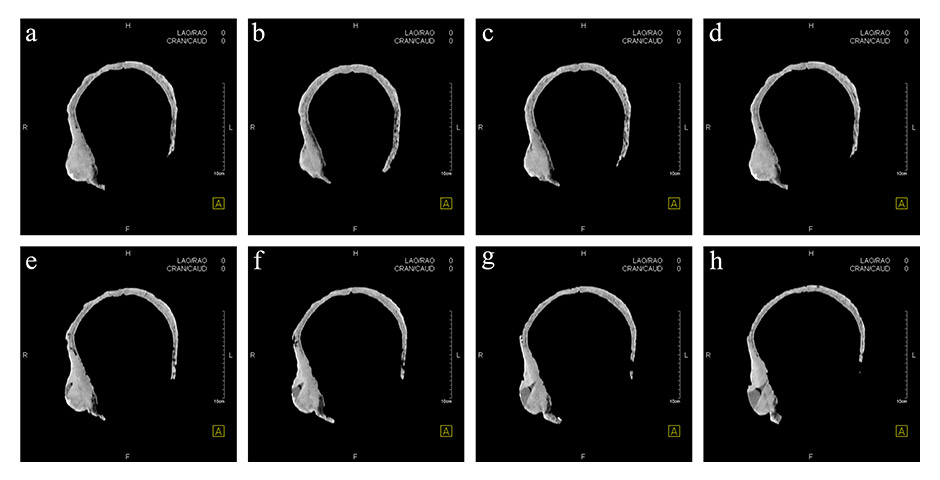

Figure 4

X-ray image of the skull.

Figure 5

Horizontal computed tomography cross-sections of the skull. Selected representative slices.

Figure 6

Computed tomography three-dimensional reconstruction of the skull. Wedge-shaped area in the centre of the lesion filled with material of lower X-ray density than the adjacent bone (green arrow).

The remains are well preserved. Morphological examination of skull and pelvis clearly classify the individual as female. The age at death was between 30 and 50 years. There is an intensely calcified bone proliferation at the right side of the os frontalis (fig. 2). Plain X-ray and CT imaging show a large (5.3 x 3 x 8.7 cm) sclerotic lesion in the area of the right temple with a partly bulging appearance (fig. 4). Figure 5 shows representative slices of the admission CT. A differentiation between tabula interna, diploë and tabula externa is not possible in major parts of the lesion. The inner boundary of the lesion shows multiple smooth-edged irregularities. There is a diffuse thickening of the right skull vault (right 7 mm, left 4 mm). The left skull vault presents a mix of sclerotic areas and areas with normal appearance with a clear differentiation between tabula interna, diploë and tabula externa. CT imaging and plain X-ray show a wedge-shaped area in the centre of the lesion that is filled with material of lower X-ray density than the adjacent bone (figs 5 and 6). Histology shows mature organised lamellar bone tissue with ordered formation of trabeculae (figs 7–9). No pathological alterations were found in the postcranial bones.

There are already several known cases of benign tumours in ancient populations. Brothwell and Sandison [10], for example, described a case of ivory osteomata in a Roman Egyptian skull. Our study presents a very unusual case of multiple osteosclerotic lesions in an Iron Age skull from Switzerland. It is the oldest known case with this kind of pathology worldwide. Analysis with various investigative methods leads to a differential diagnosis. The CT image showed that a piece of bone had been removed from the lesion earlier (fig. 5e‒h). The sampling point was then carefully reconstructed so that there was no visible trace left. It is not clear when this reconstruction of the earlier sample was done and the person who took the sample is also unknown. This work was never published or presented. In the 1950s and 1960s, one of the anthropologists in Switzerland was Erik Hug [31, 32]. His work on bone material included reconstructions just like the one in the Hochdorf skull. This could indicate that the earlier bone biopsy was performed by Erik Hug.